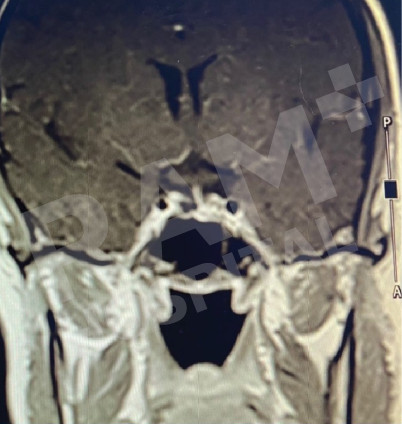

磁共振成像(MRI)可清晰、细致地显示垂体的异常病变,精准定位垂体腺瘤的位置;结合静脉造影增强检查,还能明确腺瘤的具体位置与病变性质,同时清晰呈现脑部周边组织及鼻窦的情况。这一项检查结果可为制定诊疗方案、随访评估垂体腺瘤的治疗效果,乃至规划手术方案提供明确、可靠的依据。

| 术前 | 术后 |